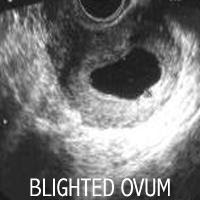

Blighted Ovum penyebab utama keguguran

Sebuah blighted ovum terjadi bila implan telur dibuahi di dalam rahim tetapi tidak berkembang menjadi embrio. Hal ini juga disebut sebagai kehamilan anembryonic dan merupakan penyebab utama kegagalan awal kehamilan atau keguguran. Seringkali terjadi begitu cepat bahwa anda bahkan tidak tahu anda sedang hamil. Sebuah blighted ovum menyebabkan sekitar satu dari dua kali keguguran pada trimester pertama kehamilan. Keguguran

adalah ketika kehamilan berakhir dengan sendirinya dalam hitungan kurang dari 20 minggu. Ketika seorang wanita menjadi hamil, telur yang sudah dibuahi menempel

pada dinding rahim. Pada sekitar lima sampai enam minggu kehamilan, embrio harus hadir. Pada waktu ini, kantung kehamilan di mana janin berkembang lebarnya adalah sekitar 18 milimeter. Tetapi berbeda dengan blighted ovum, meskipun kantung kehamilan terbentuk dan tumbuh, tetapi embrio tidak berkembang. Itu sebabnya blighted ovum juga disebut kehamilan anembryonic.

Jika anda pikir anda memiliki kehamilan normal, anda tidak sendirian, banyak wanita dengan blighted ovum berpikir begitu karena tingkat human chorionic gonadotropin (hCG) mereka dapat meningkat. Plasenta menghasilkan hormon ini setelah implantasi. Dengan blighted ovum, hCG dapat terus meningkat karena plasenta dapat tumbuh untuk waktu yang singkat, bahkan ketika embrio tidak hadir.Untuk alasan ini, tes USG biasanya diperlukan untuk mendiagnosis blighted ovum, mengkonfirmasi bahwa kantung kehamilan kosong.